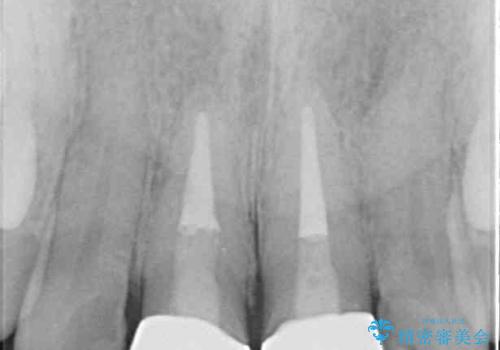

- 前歯のクラウンが着色により不自然な色となっていることを気にして来院された患者様です。

クラウンと歯の縁も合っておらず、汚れが溜まりやすい環境であったため、前歯2歯のクラウンをオールセラミッククラウンにて再補綴することとしました。